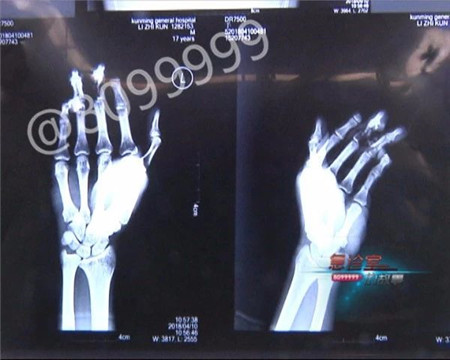

只见小伙右手除大拇指外的四个指头严重受伤,参差不齐的创口下,神经、骨骼几乎被搅碎,X光片显示之下,伤口触目惊心。

这名小伙子姓李,是一名木匠学徒,由于工作中操作不慎,手指被机器紧紧咬住。经过医生诊断,小李手指伤情严重,必须马上实施断指再接手术,且要在有限时间内进行,一旦错过了时机,就有可能影响手指成活率。

云南骨科医院手足(显微)外科 主治医生 曹学新:他伤了四个手指,小伙子挺年轻的,17岁,我们现在尽量想办法,给他把这四个手指都保全了。